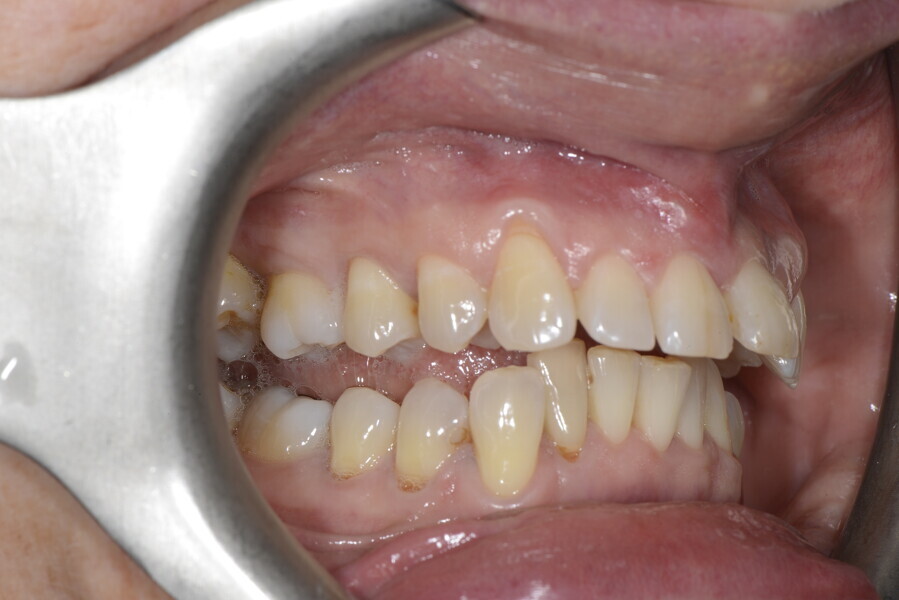

The 58-year-old patient wished to improve his oral aesthetics and function, complaining of mobility of the posterior teeth and wear of the anterior teeth. After data collection, a very complex situation was identified (Figs. 11–13):

1. severe periodontitis with poor prognosis of some teeth;

2. anterior crossbite;

3. severe wear mainly of the anterior teeth and compensatory eruption;38

4. atypical swallowing and lower posture of the tongue at rest;

5. masticatory dysfunction during the mastication test; and

6. no significant signs of temporomandibular disorder.